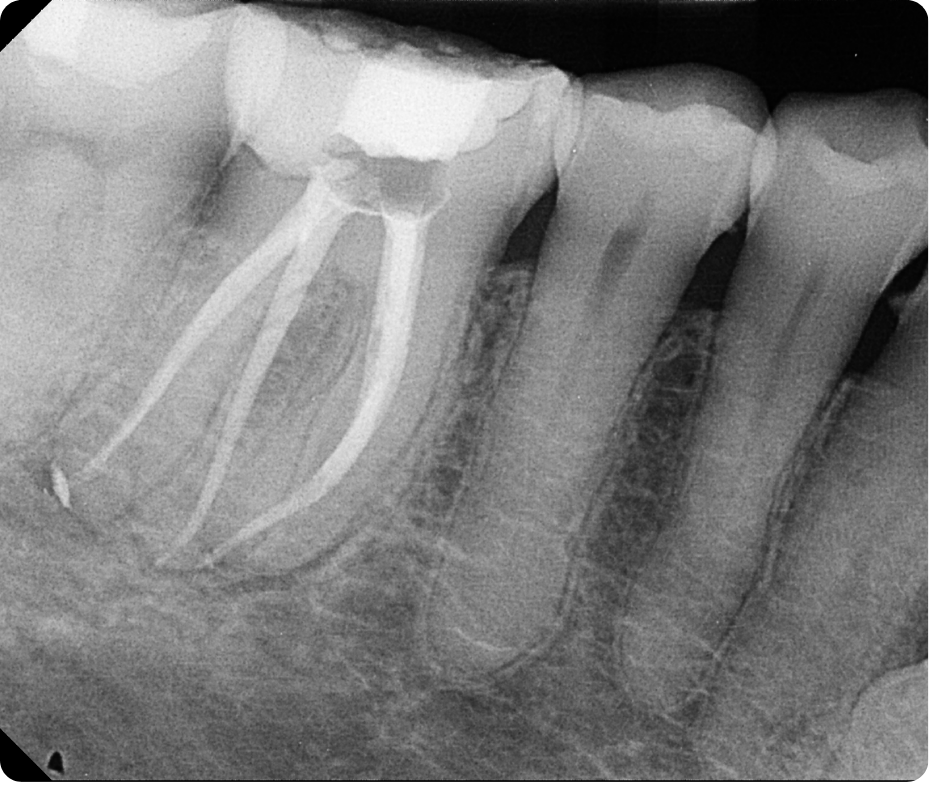

Case Study by Dr. Randy Cross

EndoScore of 3 at finish. Necrotic Symptomatic Apical Periodontitis. 2 visit with triple antibiotic paste, 30x06 conserve file with matching GP and Endoceramic sealer. Finished with bonded VistaApex clear flowable. The patient is being recalled in one year to confirm healing.

EndoScore: 3